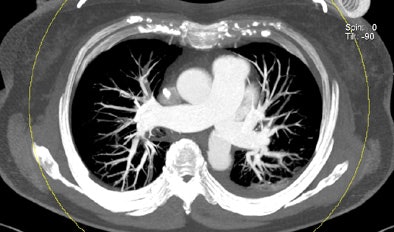

| Patient with bilateral segmental and subsegmental PE and large perfusion defects on dual-energy iodine distribution maps. All images courtesy of Dr. Ralf Bauer. |

Dual-energy CT enables the selective display of iodine distribution within the pulmonary parenchyma following contrast-enhanced pulmonary CT angiography, which in turn permits the calculation of perfusion defect (PD) size in patients with suspected PE.

The researchers measured perfusion defect size in the lung parenchyma caused by PE on dual-energy iodine distribution maps, and expressed it in two ways: as absolute quantification (VolPD in mL) and relative to the total lung volume (RelPD in %).

The limited field-of-view on dual-energy scanners was a significant drawback for dual-energy CT, Bauer noted.

"When we did lung perfusion, the analysis was restricted to the field-of-view," which is limited due to the smaller second detector on the dual-source CT scanner, he said. As a result "there were 40 patients with no coverage loss, eight patients with up to 5% coverage loss, and five patients with up to about 10% of coverage loss in the peripheral" areas of lung parenchyma, he said.